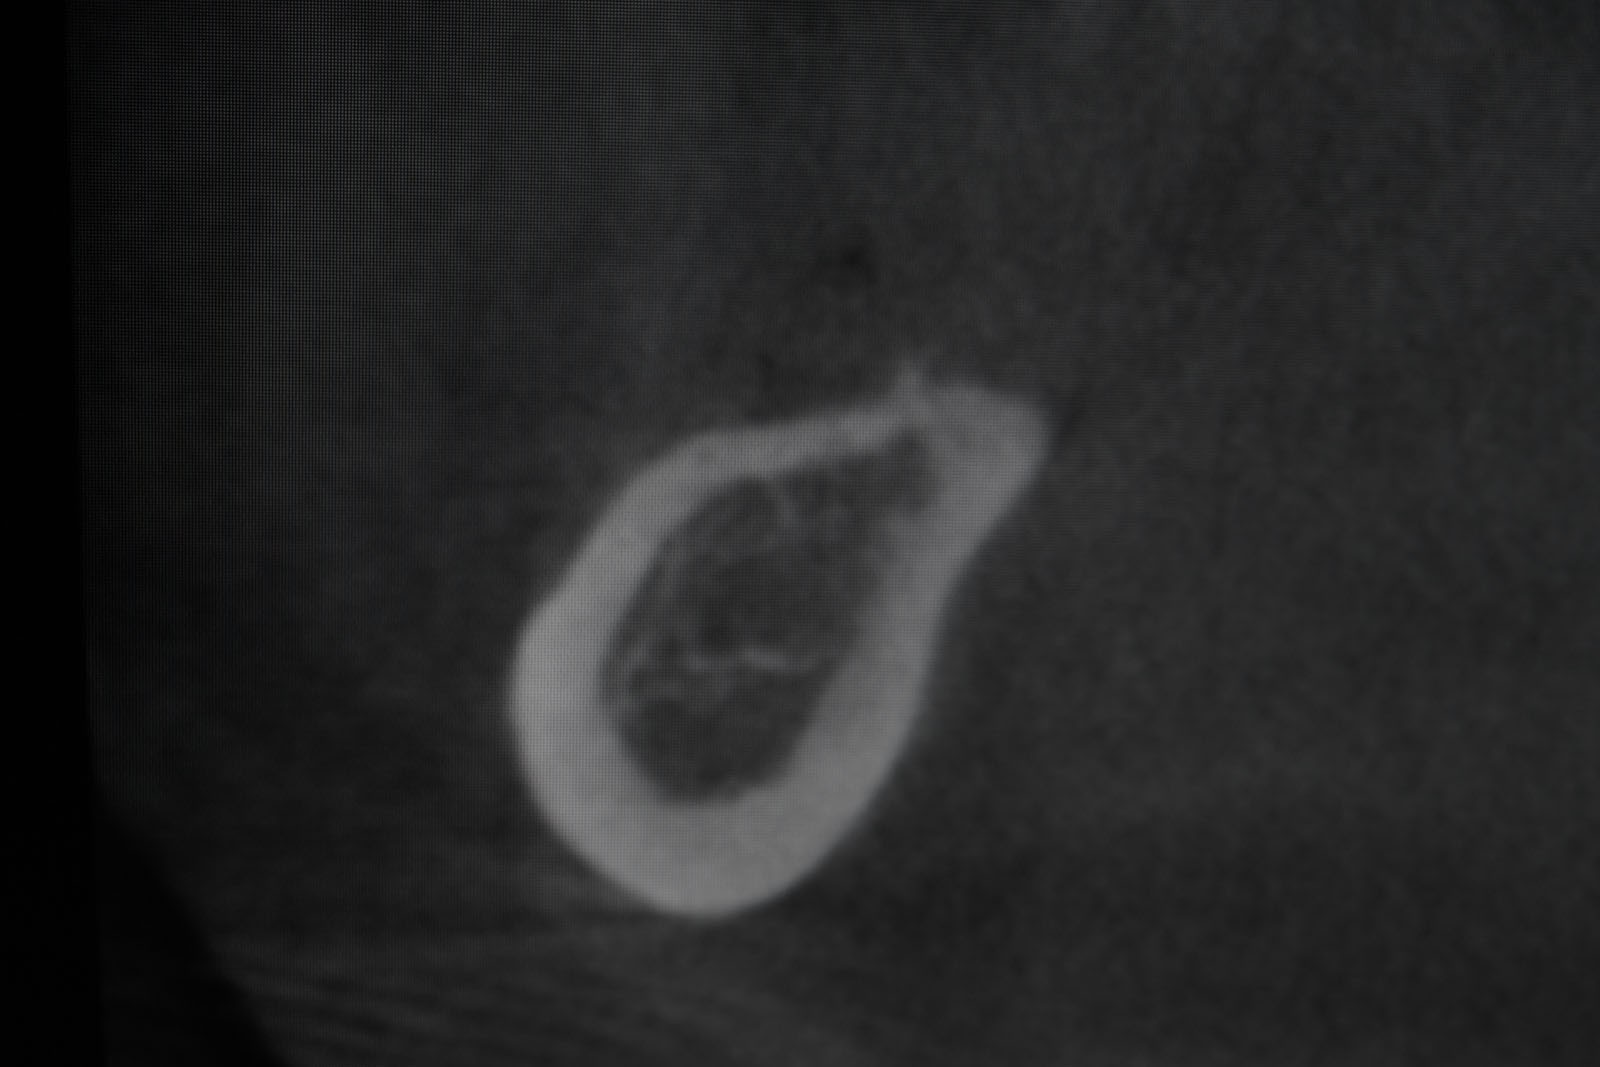

Przed podjęciem leczenia należy określić stopień zaniku kości szczęk oraz żuchwy. W tym celu przeprowadza się badanie kliniczne oraz odpowiednią diagnostykę obrazową pacjenta. Uwzględnia ona zdjęcie panoramiczne OPG jako podstawę dwuwymiarowego obrazowania podłoża kostnego oraz możliwe jest badanie tomograficzne CT lub bardziej precyzyjna tomografia stożkowa CBCT. Opcjonalnie wykorzystywana diagnostycznie tomografia pozwala na bardziej wnikliwą ocenę stopnia zaniku kości w trójwymiarowym, przestrzennym obrazie.

Precyzja projektu druku siatki bazuje na dokładności odwzorowania kształtu kości w stożkowej tomografii komputerowej CBCT, co zapewnia ich dobre przyleganie do podłoża kostnego oraz ogranicza powstawanie powikłań w postaci obnażania się siatek.